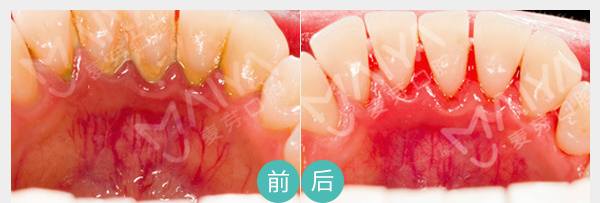

麦芽数字牙周治疗